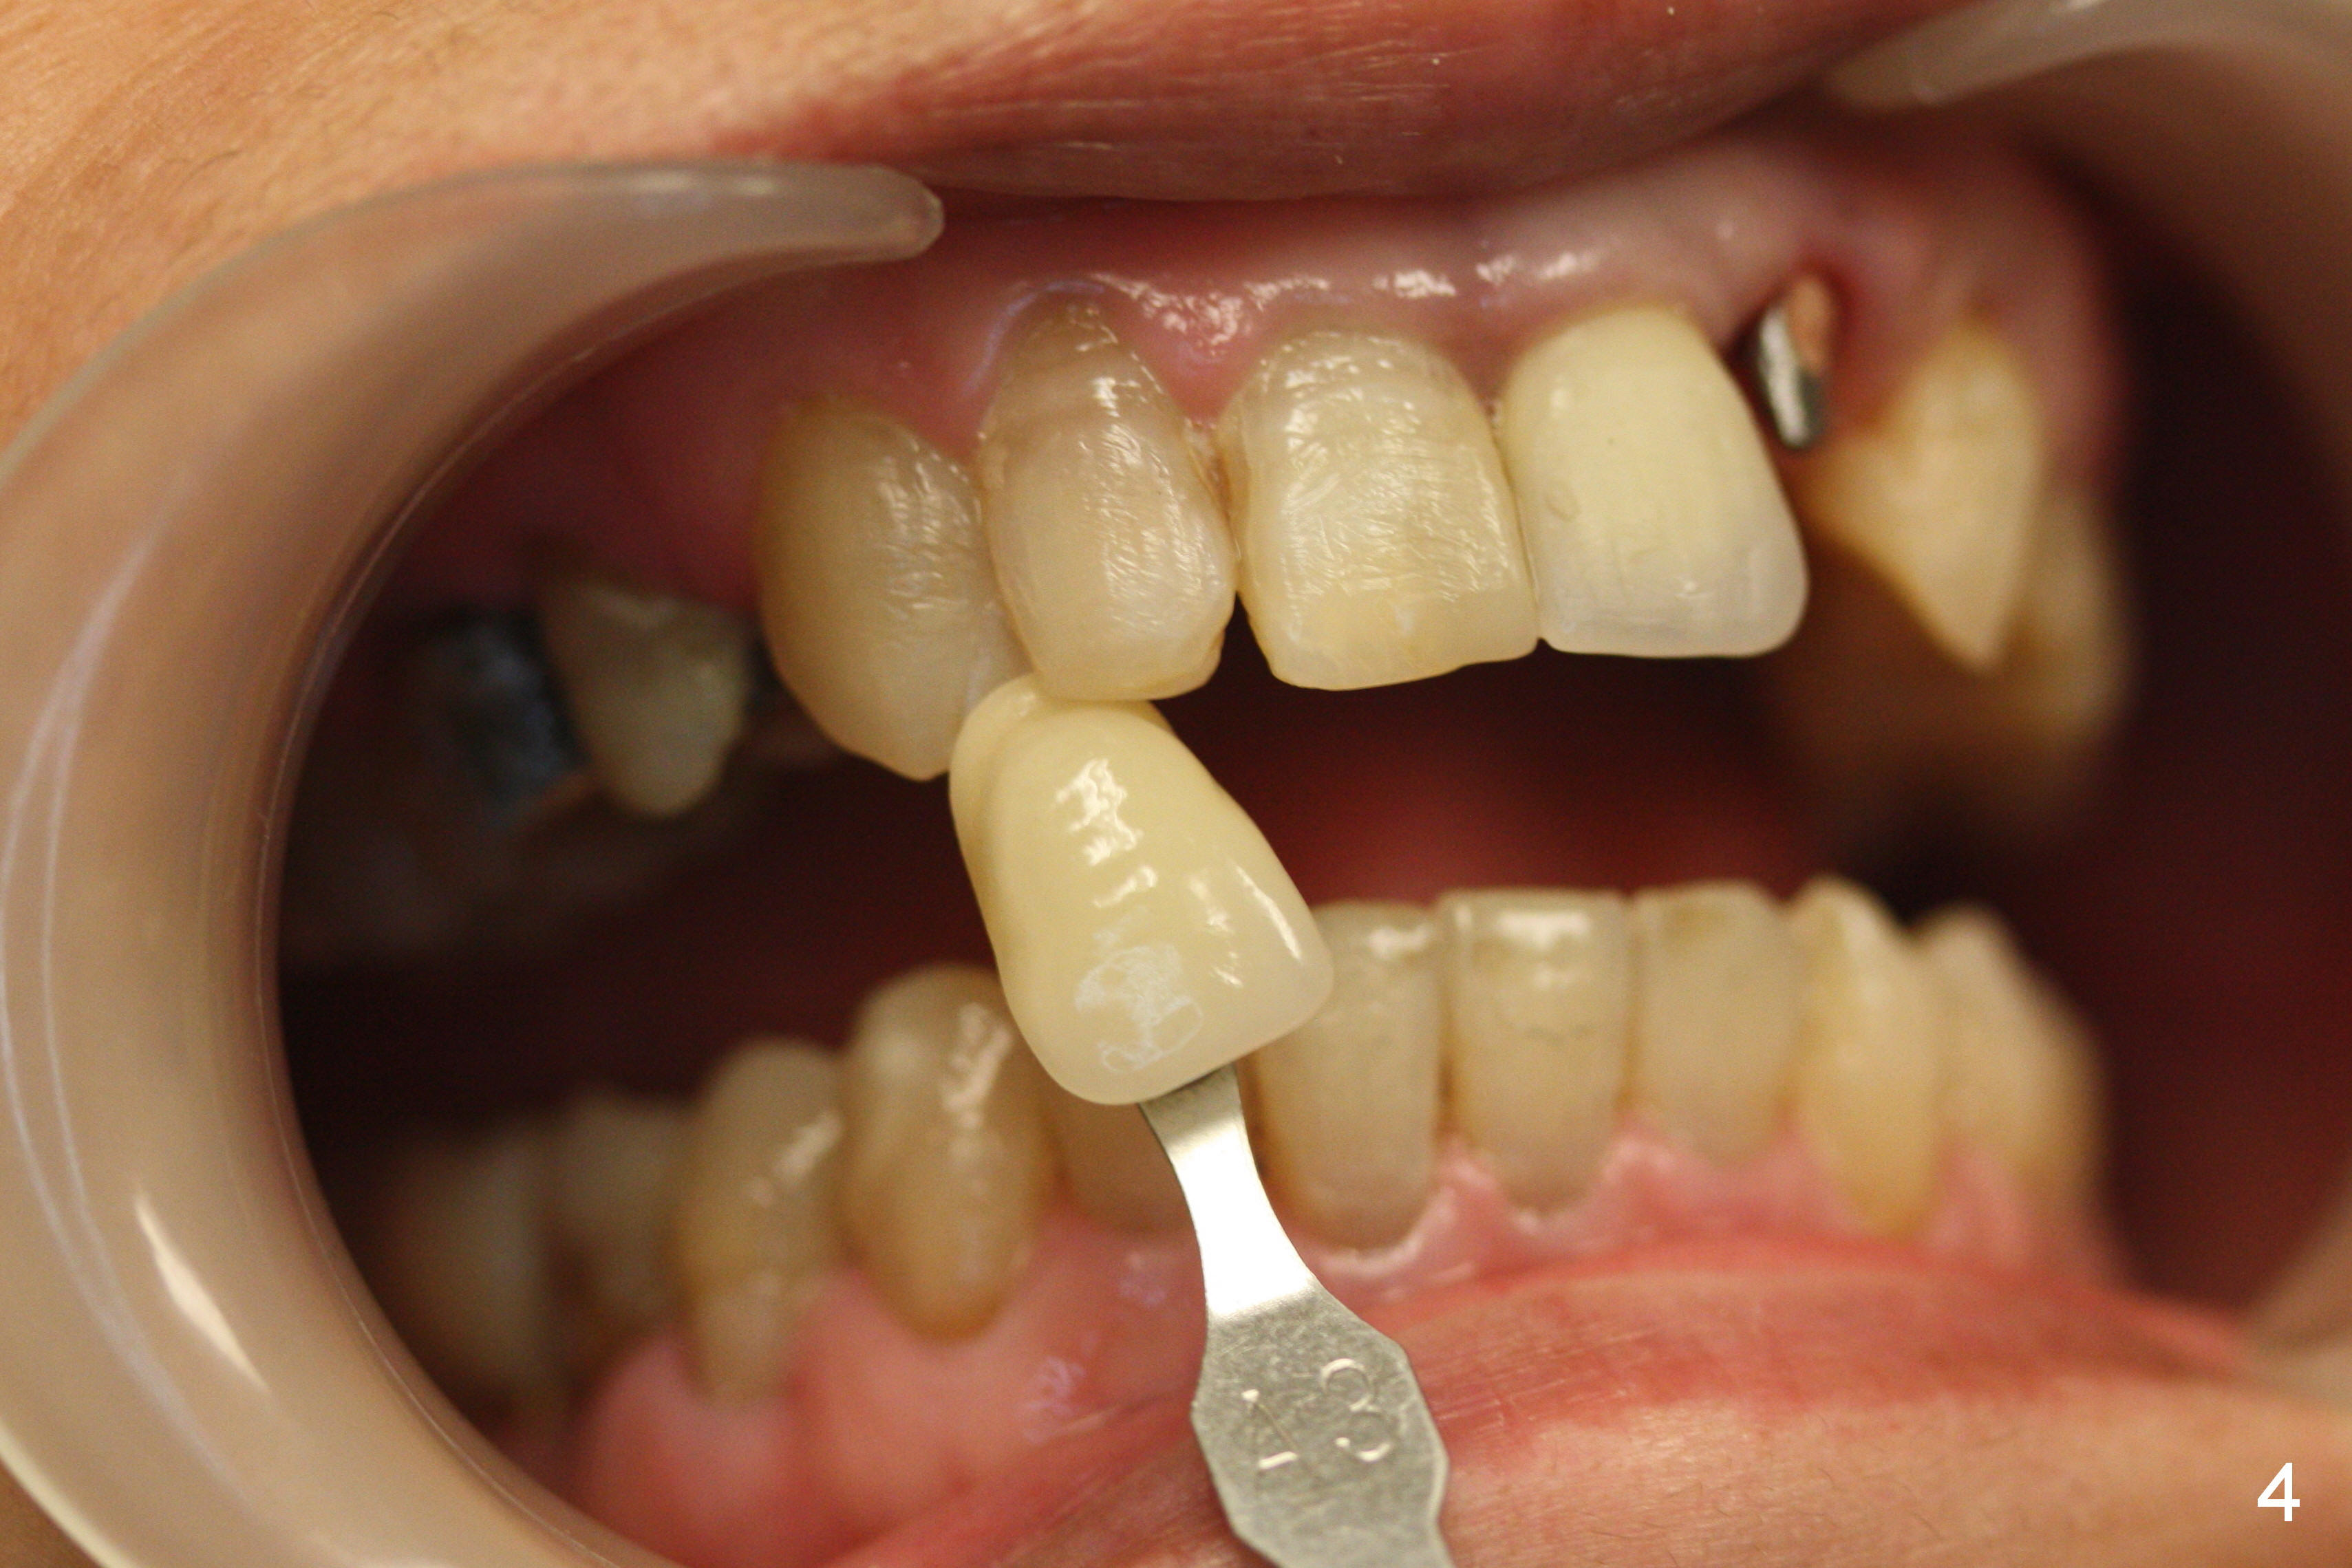

Placement of implant at the site of #10 is complicated. The trajectory is not ideal. Even though a 25 ° angled abutment is used, the abutment is still too buccal. Since the implant is placed deep (Fig.1,2), the margin is high (Fig.3). The margin of the crown should be thin and able to cover the Cavit as much as possible (Fig.3 C).

Fig.4, 5 shows shades against the teeth #7 and 10.